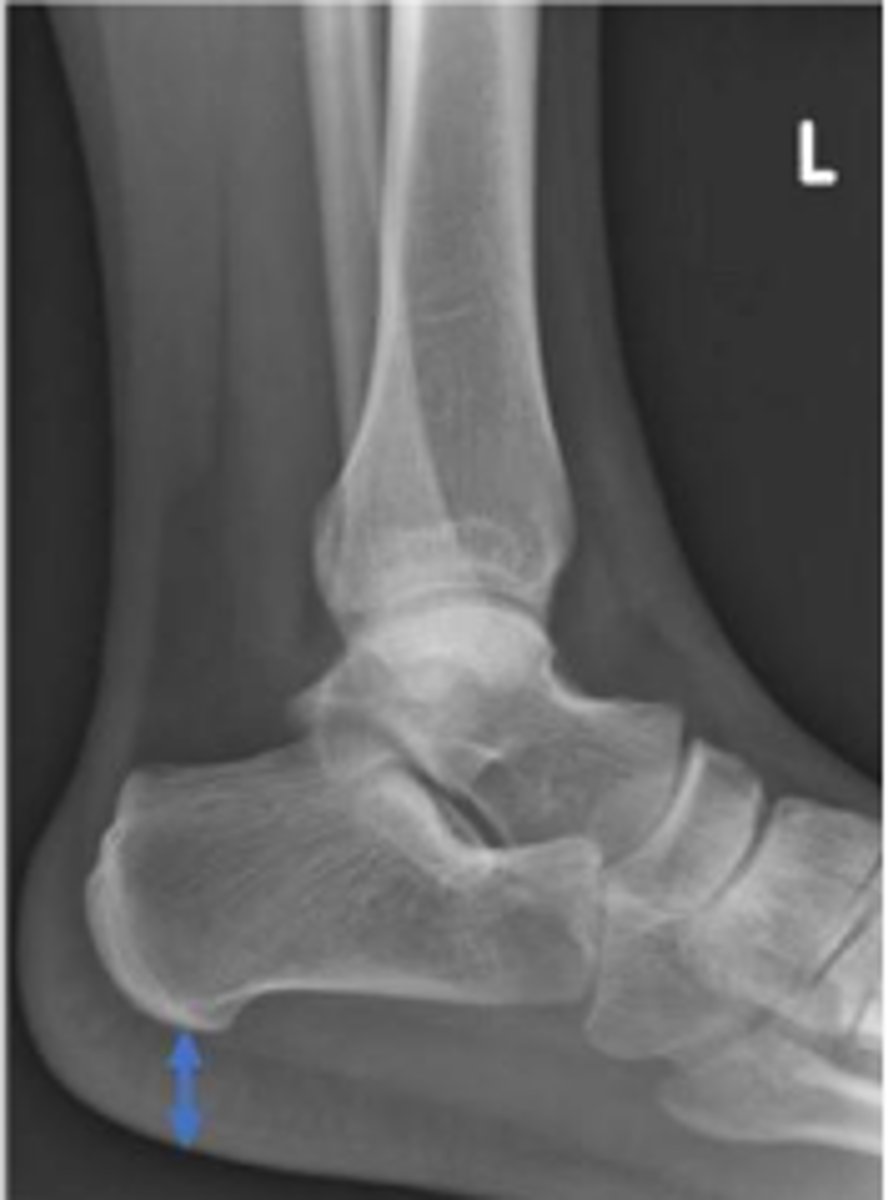

Heel pad measurement

What is the name of the assessment?

Females: average 19mm (maximum of 23mm)

Males: average 19mm (maximum of 25mm)

What is the normal range for the assessment?

Achille's tendon thickness

4-8mm

Yes

Is the assessment within normal limits?

Overuse, ill-fitting shoes, tendinosis/tendinitis,

rheumatological diseases, etc.,

Name 2 conditions that may result in an increase in the measurement beyond the upper limit of normal ?